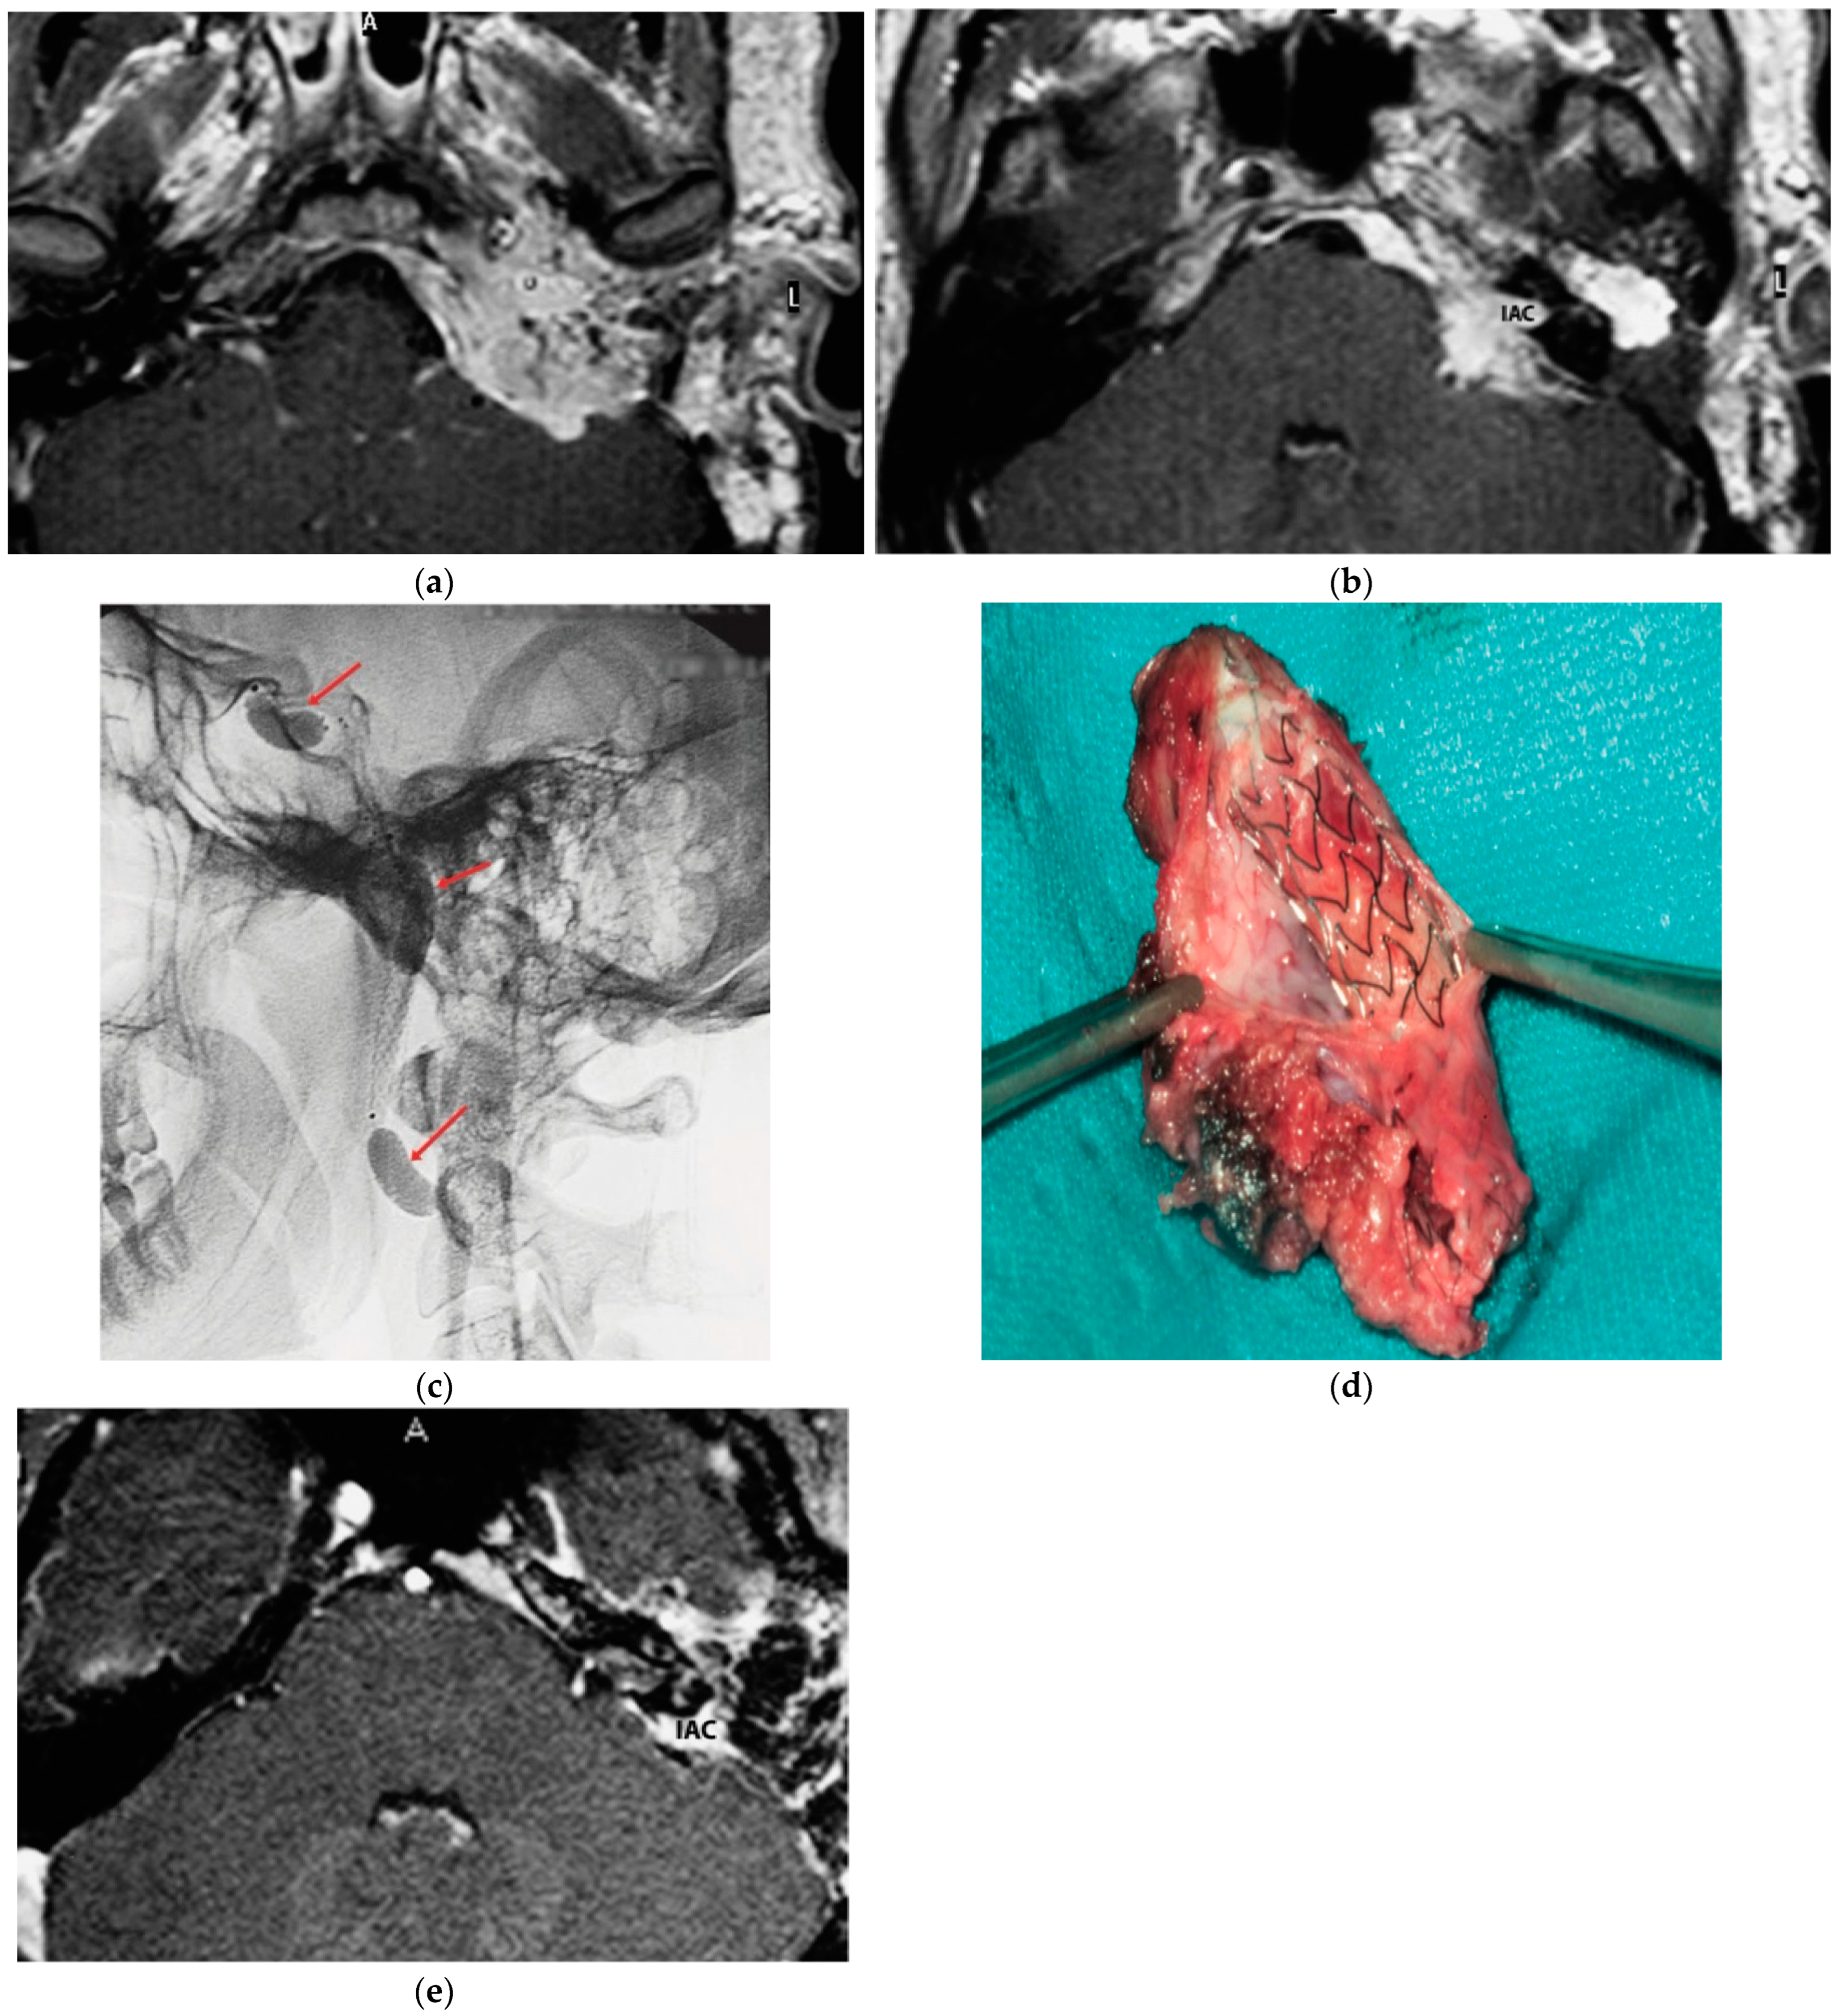

5.1. Case 1: (C4Di2)

5.2. Case 2: (C3Di1 + Stage I VP)

5.3. Case 3: (C4Di2Vi)

5.4. Case 4: (C3Di2 + Stage II Vagal PGL)

5.5. Case 5: (C3Di2Vi)

5.6. Case 6: (C4Di2Vi)